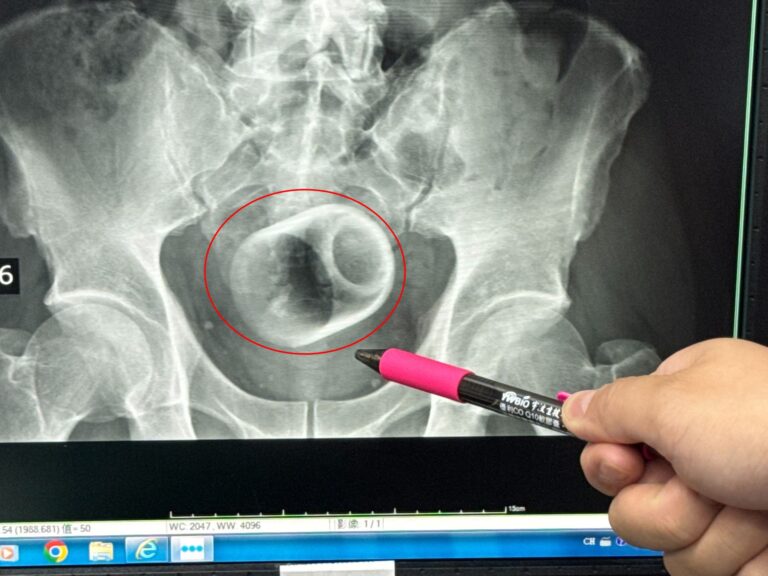

兩處 UCC 均具備 X 光、超音波及基礎檢驗設備,若醫師判斷需進一步治療,也能透過「綠色通道」立即後送至鄰近醫學中心,讓整體醫療流程更順暢。